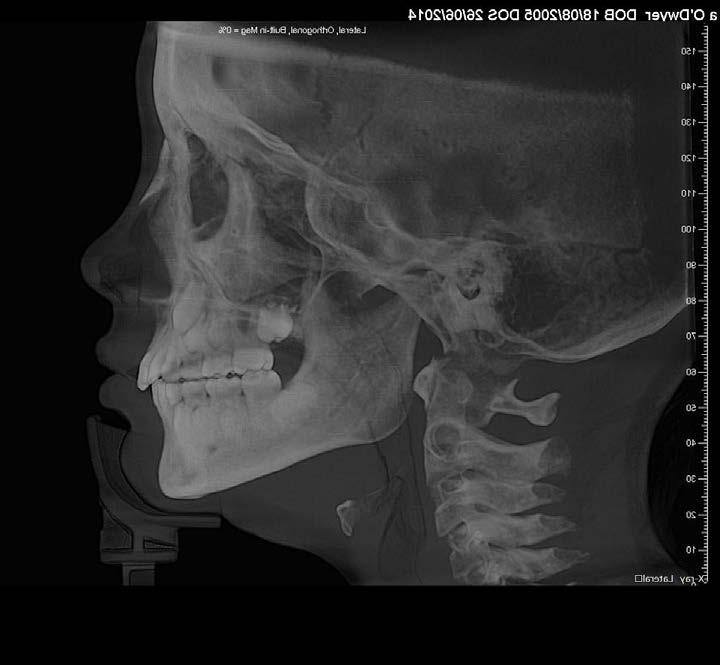

Lateral Cephalometric radiogram and tracing revealed robust lower airway (18.0/15mm), CVMS 6, maxilla and mandible are prognathic (SNA - 93° and SNB - 84°), Class II skeletal (ANB –9.0 mm, Witts – 9.0 mm). The patient was hyperdivergent (NS/ GoM – 30°, ALFH - 83 mm!!), protrusive maxillary incisors (U1/ SN – 117.0°), mandibular incisors were within the norm (L1/GoM 95.0°) and Harvold Δ was 30 mm. The soft tissue profile (lips) was convex (Figure 5-C, D).

FIG. 5C: Pre-treatment, Cephalometric radiogram

FIG. 5D: Pre-treatment,Cephalometric tracing